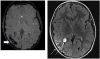

Axial MRI images from the same individual with Sturge-Weber syndrome showing typical imaging findings of loss of signal on susceptibility-weighted imaging in the right parietal-occipital region, indicating calcification (thick arrow, left panel) and leptomeningeal and choroid plexus enhancement (thin arrow, right panel).